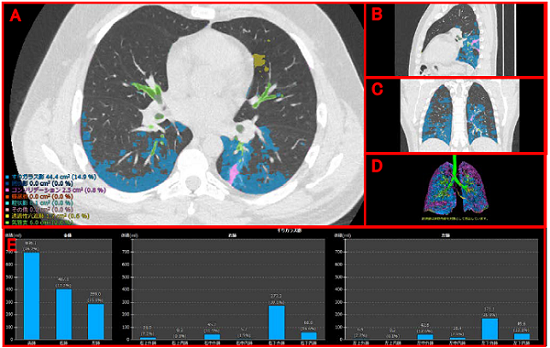

富士フイルム(株)の間質性肺炎の定量化技術は、AI技術を用いて設計したソフトウエアが、CT画像から肺野(はいや)※2内の気管支、血管、正常肺および、網状影やすりガラス影、蜂巣肺(ほうそうはい)※3など肺の7種類の病変性状を識別し、自動で分類・測定することで、間質性肺炎の病変を定量化するものである。さらに、肺野内における病変の分布と進行状態を詳細に確認できるよう、肺野を12の領域※4に分割し、その領域ごとに、病変の容積および割合を表示する。

A:CT画像のアキシャル像(体を横に切った像)

B:サジタル像(体を縦に切った像)

C:コロナル像(体を前後に切った像)

D:3D画像それぞれに、病変の識別結果を表示

E:指定した病変がどの領域にどの程度発生しているかをグラフで表示